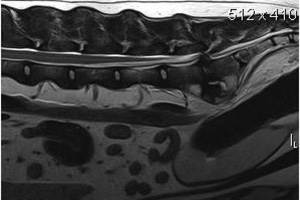

В любом случае, какова бы ни была причина заболевания: врожденная аномалия или дегенеративные процессы, для постановки диагноза необходима рентгенография, миелография, компьютерная томография или МРТ.